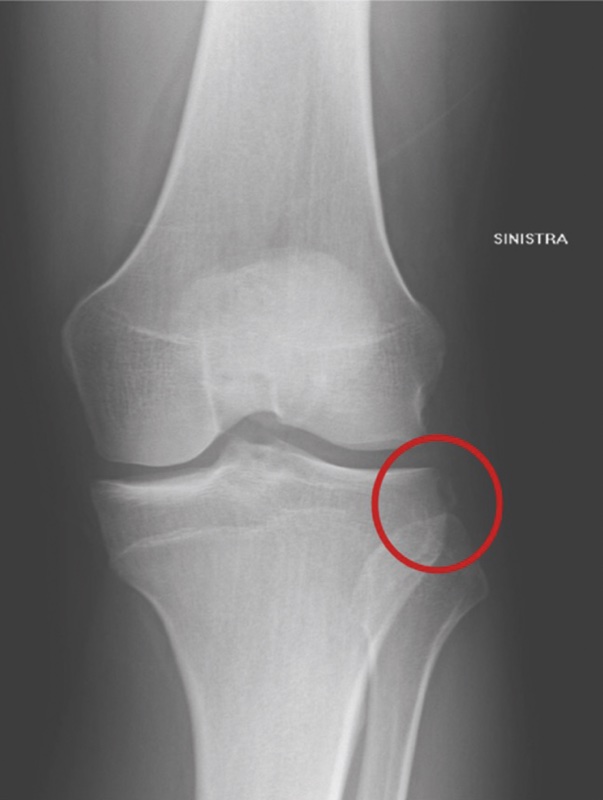

La valutazione radiografica sicuramente può fornire ulteriori informazioni, oltre che identificare altre lesioni. Nelle radiografie con proiezione AP si può evidenziare la frattura di Segond (Fig. 1) 8, segno indiretto di lesione del LCA in cui si ha l’avusione nel piatto tibiale esterno di un piccolo frammento da parte del legamento antero-laterale.